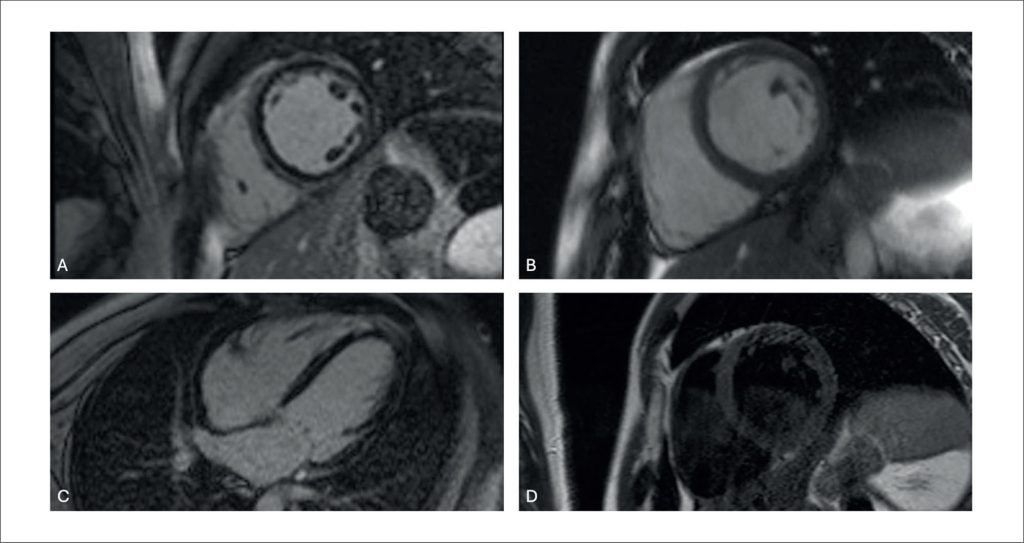

Long-term Follow-Up of a Patient with FLNC Gene Mutation-Related Cardiomyopathy: A Case Report

Heart Failure (HF) is estimated to affect approximately 26 million people worldwide., In Brazil, prevalence is high, with about 2 million diagnosed patients and an incidence of roughly 240,000 new cases every year. Between 2011 and 2021, more than 2.5 million HF-related hospitalizations were recorded in the Brazilian Unified Health System (SUS), underscoring the relevance of the disease in the national context. These figures highlight the need for early diagnostic strategies and etiological definition for the appropriate management of these patients. Establishing an etiological diagnosis is often challenging but essential to provide disease-specific treatments and improve prognosis. Diagnosis encompasses multimodality cardiac imaging, with Cardiac Magnetic Resonance imaging (CMR) being a useful tool for evaluating non-ischemic cardiomyopathy phenotypes and establishing an etiological diagnosis.